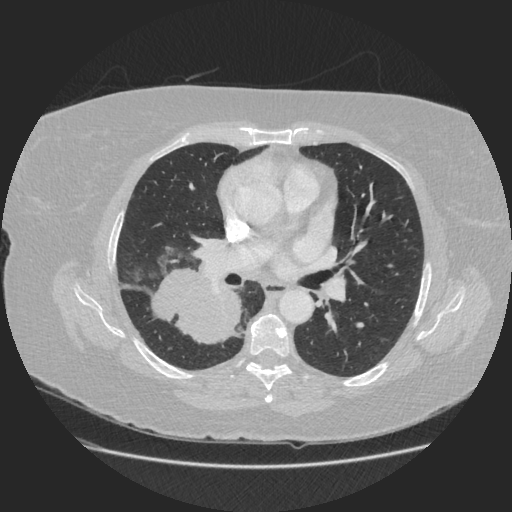

Figure 1: Preoperative CT scan

In this case, the preoperative CT demonstrated a 6 cm central tumor crossing the oblique fissure between the upper and lower lobes. The case was discussed at the authors’ tumor board, and a right pneumonectomy was recommended. Mediastinal nodes, sampled by EBUS/EUS, were negative.